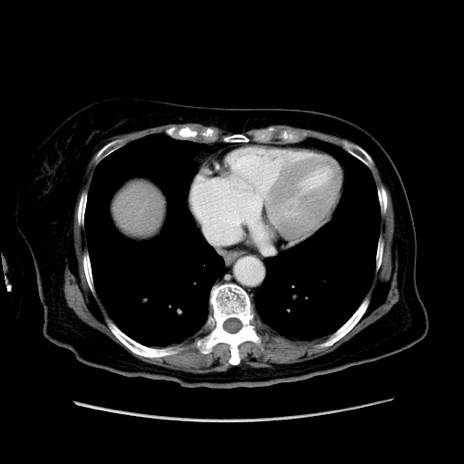

症例19(横断像)

【症例】80歳代女性

【主訴】下腹部痛

【現病歴】約8時間前より下腹部痛の出現あり、救急外来受診。

【既往歴】両側付属器切除

【身体所見】意識清明、下腹部正中に手術痕あり、その部位に一致して圧痛と反跳痛あり。腸蠕動音は亢進。

【データ】WBC 9300、CRP 0.15